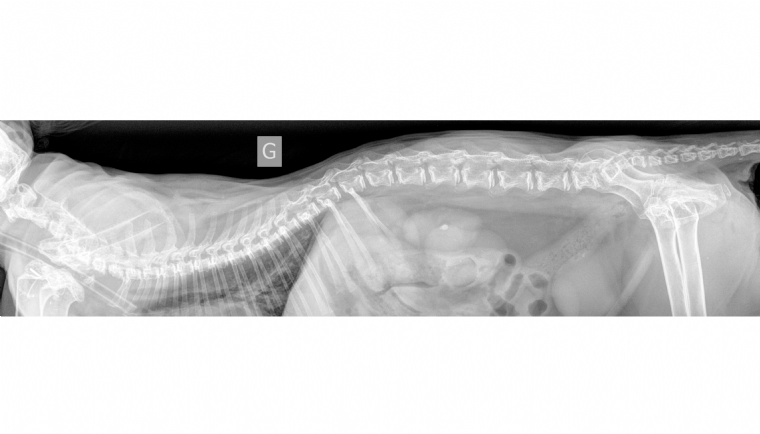

Mercredi 20 Fevrier 2019 Animaux de compagnieRadiographie du rachis : projection latérale.

Un chat européen mâle de 4 ans est présenté pour un retard de croissance et des difficultés locomotrices présents depuis la naissance mais de dégradation récente.